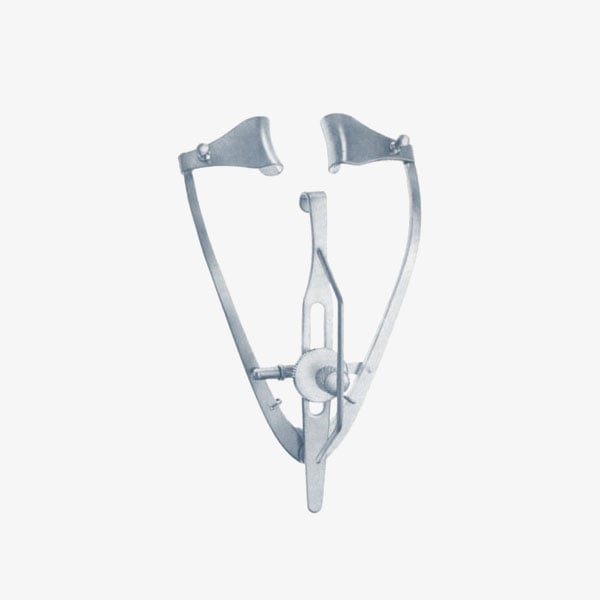

Speculums

Categories: Ophthalmic Instruments, Speculums